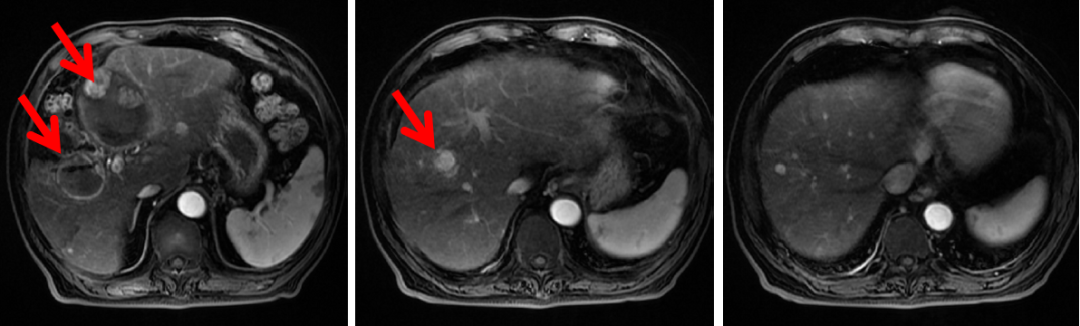

腹部CT:肝IV段(8.8×6.6 cm)和肝V-VIII段(4.5×3.7 cm)肿块,考虑HCC,其中肝IV段肿块伴出血、破裂,余肝内多枚强化结节。

诊断:肝癌TACE术后肝内复发转移伴破裂,BCLC C期,Child-Pugh A级。

图1:2019年5月21日,给予替雷利珠单抗前腹部CT横断位(A、B、C)和冠状位(D)